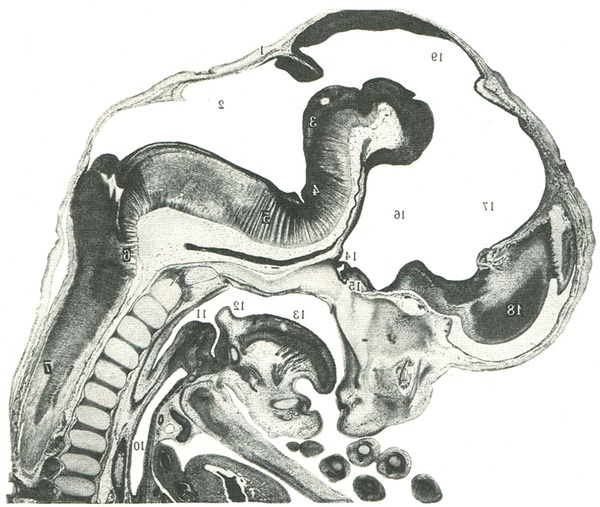

492. Сагітальний розріз ембріона на 10-11-й тижня розвитку (за Ю. Р. Шевченка).

1 - перешийок мозку; 2 - порожнина заднього мозку; 3 - поздовжній задній пучок; 4 - міст; 5 - поперечні шляху до ядер моста (від кори до ядер мосту); 6 - пірамідні шляхи; 7 - спинний мозок; 8 - спинномозковий вузол; 9 - хребетний стовп; 10 - трахея; 11 - стравохід; 12 - надгортанник; 13 - мова; 14 - гіпофіз; 15 - гіпоталамус; 16 - порожнина проміжного мозку; 17 - порожнина кінцевого мозку; 18 - кінцевий мозок; 19 - середній мозок.

Стадія розвитку трьох мозкових міхурів відзначається на 4-5-му тижні внутрішньоутробного періоду. Бульбашки отримали назву: передній (prosencephalon), середній (mesencephalon), ромбовидний (rhombencephalon) (рис. 492). Вони відрізняються один від іншого по вигинах і звужень, деформуючим мозкову трубку не тільки зовні, але і її порожнину. Стінку мозкових міхурів утворюють три шари: 1) матричний шар, або зародковий, що складається з малодиференційованих клітин; 2) проміжний шар; 3) крайової шар, що має мало клітинних елементів. У вентральній стінці мозкових міхурів добре розвинений проміжний шар, з якого в подальшому утворюються численні ядра, а дорсальна стінка майже позбавлена їх. Передній нейропор закривається безструктурної замикальної платівкою. В області латеральної стінки переднього мозкового міхура, у якому закладаються очні чаші, матричний шар клітин подвоюється і розширюється, утворюючи сітківку очей. Очні бульбашки формуються в місці поділу переднього мозкового міхура на дві частини. У цей же період розвитку задня частина мозкової трубки, відповідна спинного мозку, має внутрішній эпендимальный і зовнішній ядерний шари, більш компактні на вентральній стінці. На вентральній стінці мозкових міхурів формується вентральная мозкова складка, сприяє звуження порожнини мозкових міхурів. Так само відбувається закладка воронки і гіпофіза на вентральній стінці переднього мозкового міхура (рис. 492).

На 6-7-му тижні ембріонального розвитку настає період формування п'яти мозкових міхурів. Передній мозок поділяється на кінцевий мозок (telencephalon) та проміжний мозок (diencephalon). Середній мозок (mesencephalon) не ділиться на вторинні бульбашки. Ромбоподібний мозок поділяється на задній мозок (metencephalon) та довгастий мозок (myelencephalon). У цей період мозкова трубка сильно вигнута і передній мозок нависає над роговий бухтою і серцем. У нервовій трубці розрізняють вигини: 1) тім'яної вигин, має опуклість в дорсальном напрямку на рівні середнього мозку (рис. 492); 2) вентральний мостовий виступ на рівні моста; 3) потиличний вигин, по розташуванню відповідний рівню спинного і довгастого мозку.